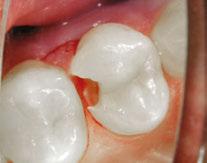

A 10-year-old female patient with a history of swelling and pain associated with tooth No. 20 was referred to our office. The patient exhibited severe dental anxiety. Upon clinical evaluation, a dens evaginatus was noted on the occlusal surface of the tooth (Figure 1). The tooth was sensitive to percussion, palpation, and bite stick while cold testing yielded no response. A periapical radiograph and CBCT scan (Carestream 9600) revealed a wide open apex and evidence of apical periodontitis, leading to the

Figure 1 (left): Dens evaginatus noted on the occlusal surface. Figure 2 (right): Preoperative periapical radiograph of tooth No. 20 showing evidence of apical periodontitis and a wide open apex

diagnosis of a necrotic pulp and symptomatic apical periodontitis of tooth No. 20 (Figures 2 and 3).